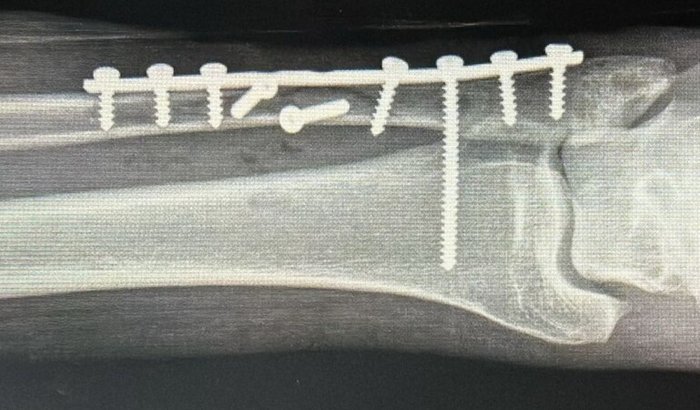

No dia 25 de dezembro sofri um acidente a quebrei a fíbula tive que fazer uma cirurgia com.placa e parafuso desde então estou sem trabalhar